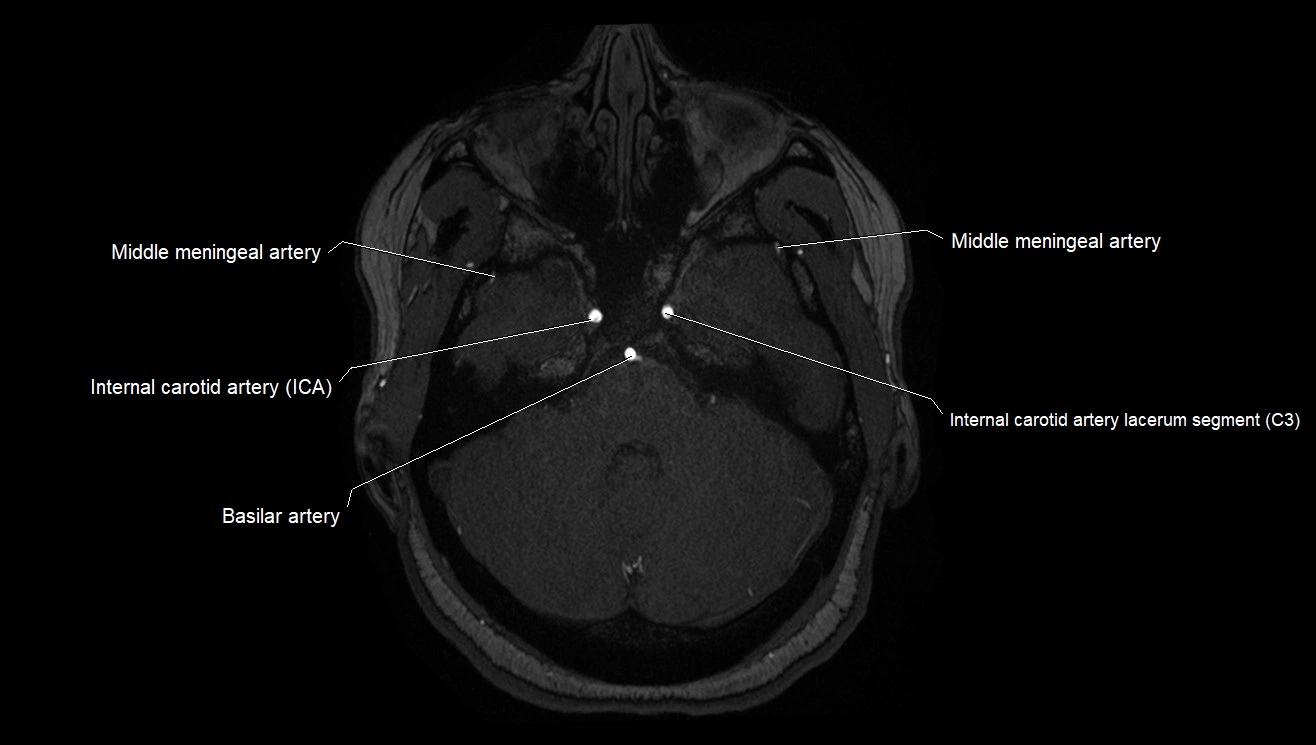

MRA (Magnetic Resonance Angiography):

• Flow-related enhancement makes the AChA appear as a bright, linear vascular signal against suppressed background

• High sensitivity for origin and proximal course; distal branches may be too small to resolve

• Detects stenosis, occlusion, aneurysm, AVM feeders

CTA (CT Angiography):

• Opacified with iodinated contrast, AChA appears as a bright high-attenuation vessel

• Visualized from ICA origin along optic tract toward choroid plexus

• 3D reconstructions depict its course and relation to adjacent arteries

• Gold standard for identifying aneurysms, occlusion, or vascular anomalies